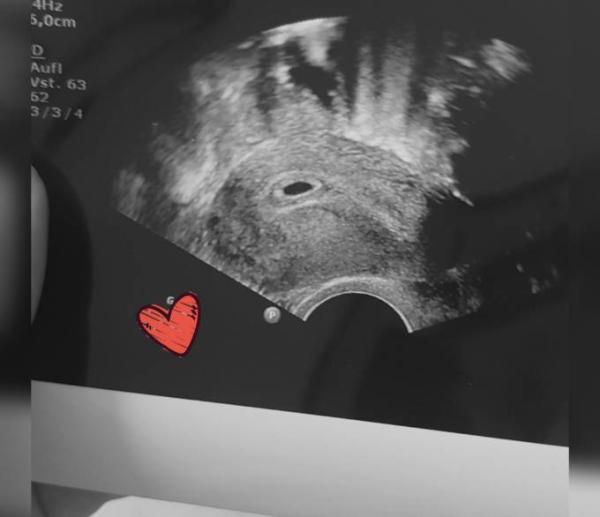

Hallo ihr lieben:) ich bin auch dabei . War gestern beim beim vertretungs Frauenarzt da meine momentan urlaub hat und der hat ein Ultraschall gemacht. Bin momentan in der 6.woche und so aufgeregt das ist meine erste ss.. bin examinierte Altenpflegerin und merke jetzt schon es ist ein wenig anstrengend durch die Müdigkeit und und und.. und bin daher auch sehr vorsichtig was das heben etc angeht. Ich hoffe ich bekomme nächste Woche ein Termin bei meiner Frauenärztin und sie schaut dann nochmal nach ob alles ok ist mit meiner Erbse , den Herzschlag konnte ich leider noch nicht sehen.. aber dieses Warten macht mich hibbelig.. und hoffe dann das ich dann auch demnächst den Mutterpass in den Händen halten kann LG an alle werdenden Muttis und eine schöne Kugelzeit

Bild zu Ich bin auch dabei :) - Forum für Januar - Mamis